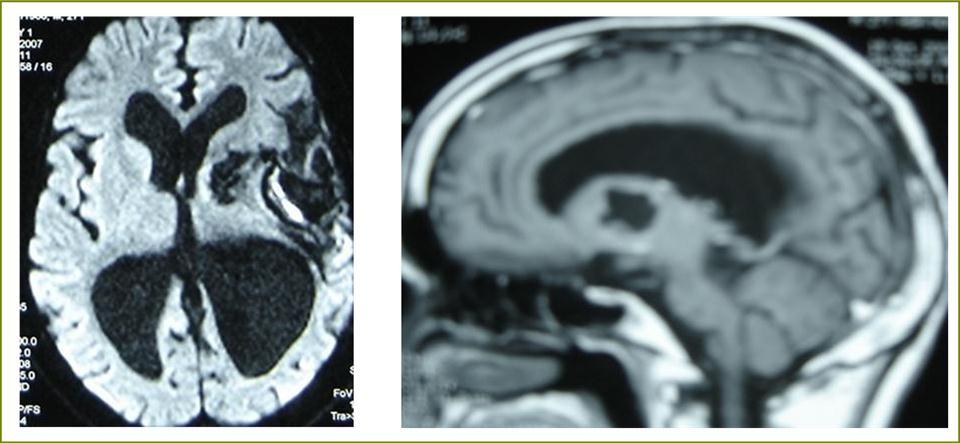

A 27 years-old male patient was admitted with 1 month history of headache, fever, short term memory lack, aphasia, right hemiparesis and seizures. He had liver hydatid cysts excised 8 years before and was treated with adjuvant medication (albendazole). The neurological examination revealed right central third cranial nerve palsy and hemi paresis, with Babinski sign positive, aphasia and papilledema on ocular fundus. The Glasgow Coma Scale was evaluated to 10/15 (E:3; V:1; M:6). A brain CT scan showed a large left temporoparietal intracerebral multiple and calcified hydatid cysts, important mass effect with midline shift about 7 mm following by an obstructive hydrocephalus (Figure 1). Other cysts were found in thalamic region (Figure 2). The Thoraco-abdominal CT scan showed multiple intra peritoneal hydatid cysts (Figure 3). A left temporo parietal craniotomy was performed in emergency. After corticectomy, using Arana-Iniguez technique, the appearance of the capsule suggested infected hydatid cysts with a purulent material which was aspirated. Numerous hydatid cysts were lifted away and several daughter vesicles were carefully removed without rupture (Figure 4). Macroscopically, the abscess wall appeared to be thick, calcified and tightly attached to lateral ventricular, so it could not be removed. The deep cyst overlying the third ventricle was left.in place. Microscopic examination demonstrated live scoleces, protoscoleces and multiple hooks. These findings are consistent with hydatid cyst (granulosis ecchinococcus) (Figure 5). Bacteriology examination found several white blood cells in the pus (neutrophilia) and infection by streptococcus pneumonia. This was consistent with infection. After surgery, the patient had medication (albendazole, specific antibiotherapy and phenobarbital). The inflammation assessment in the blood showed leukocytosis, a high C-reactive protein rate and increased erythrocyte sedimentation rate. Post operative CT scan was performed and showed the residual calcified capsule and decreased ventricular size (Figure 6). Clinical improvement was achieved after treatment. One month after the initial diagnosis, CT scan of the brain showed no recurrence and a physical examination revealed a neurologically intact, fully functional patient and eyes fundus normal. He was discharged and went to abdominal surgery two months later with complete intra abdominal cysts removal. Albendazole treatment was continuing for six months and radiological exploration was performed by brain MRI with spectroscopy at three and six month later. This showed that infection had resolved and the deep cyst overlying the third ventricle is less spherical (Figure 7, Figure 8). Four years later, the outcome was good.

Figure 8.sagittal T1 C+ MRI and axial spectroscopy showing the residual capsule and deep cyst which is less spherical.